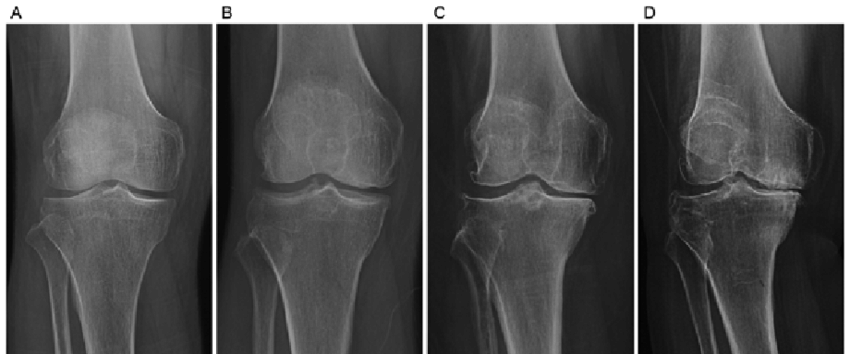

Grade를 각각 자세히 보게되면

0은 정상

1은 JSN(joint space narrowing)나 작은 골극이 생길수 있고 (fibrillation, disruption)

2부터는 JSN 가능성이 1보다 높아지고, 명확한 골극이 관찰됩니다.

3부터는 여러 골극과, 중등도 JSN와, 뼈의 변형, 연골하골 경화의 관찰이 있을 수 있습니다.

마지막 단계인 4의 경우 큰 골극과, 매우 명확한 JSN, 심한 연골하골 경화, 뼈의 심한 변형 등이 있을 수 있습니다.

아래 여러 사진을 보면서 한번더 확인해보면 0에서 4로가면서 관절간격도 좁아지며, 골극과, 뼈의 변형이 더 심해지는 것을 알 수 있습니다.